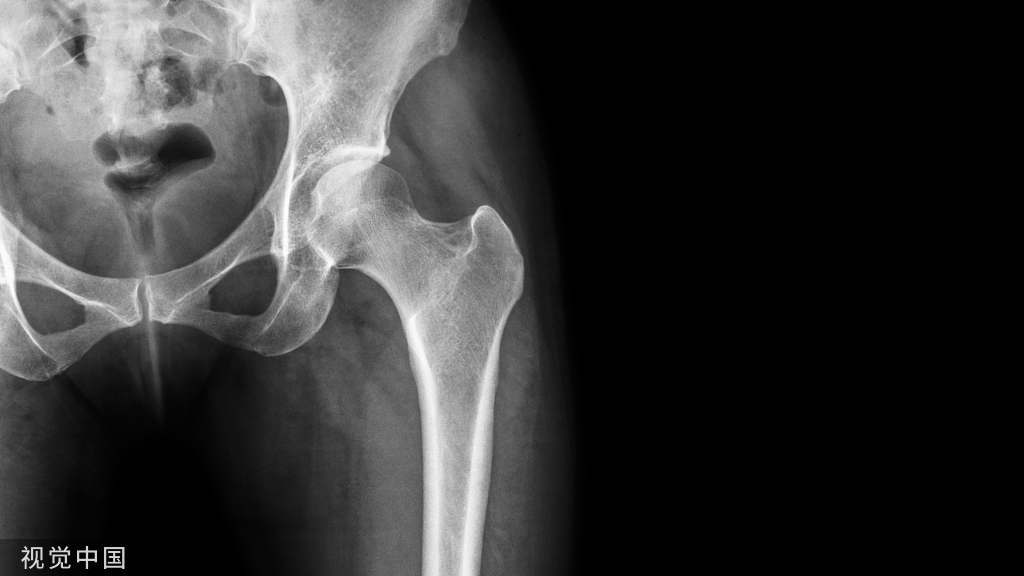

【影像表现】:X线骨盆正位示右侧股骨颈骨折,断端相互嵌入【影像诊断】:右侧股骨颈嵌入型骨折。